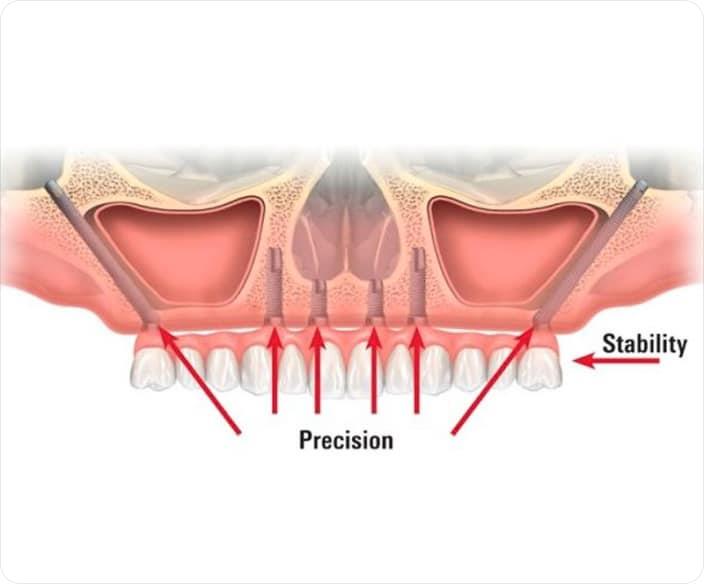

A special type of dental restoration is referred to as zygomatic implants, which are designed for patients with severe maxillary bone loss. These fixtures are surgically placed within the zygomatic bone, commonly known as the cheekbone, unlike conventional implants that are anchored in the jawbone. This alternative approach provides stability when traditional implantation isn’t possible because the bone structure doesn’t allow for conventional implants, and there’s no way to place them due to inadequate bone support. This allows for the creation of a stable foundation for the Dental prosthesis without any requirement of bone grafting. These implants are longer than traditional dental implants.

- Initial evaluation and surgical planning – when you reach out to our Dental clinic, the dentist or the surgeon will conduct a thorough examination and take scans like 3-D imaging cone beam CT scans, Digital intra-oral scans to assess your bone structure and plan the implant placement.

- Surgical placement – the surgery is performed under general anaesthesia or under local anesthesia. The type of Anesthesia depends on the patient’s and surgeon’s comfort ability. The surgeon makes small incision in the gum tissue and carefully dissect to reach the bone and places the zygomatic implants into the cheekbone. It is placed in a planned angulation and depth. In complicated cases a surgical guide is utilized to place the Implants.In many cases a temporary processes can be loaded immediately allowing you to leave the clinic with a full functional smile.

- No need for bone grafting– since the implants are placed in the cheekbones that are already very strong there is no need for a bone grafting procedures.

- Reduced treatment time – there are two reasons for reduced treatment time that is : elimination of bone grafting which itself saves 3 to 6 months of time and possibility of immediate loading with temporary teeth which shortens the overall treatment duration.